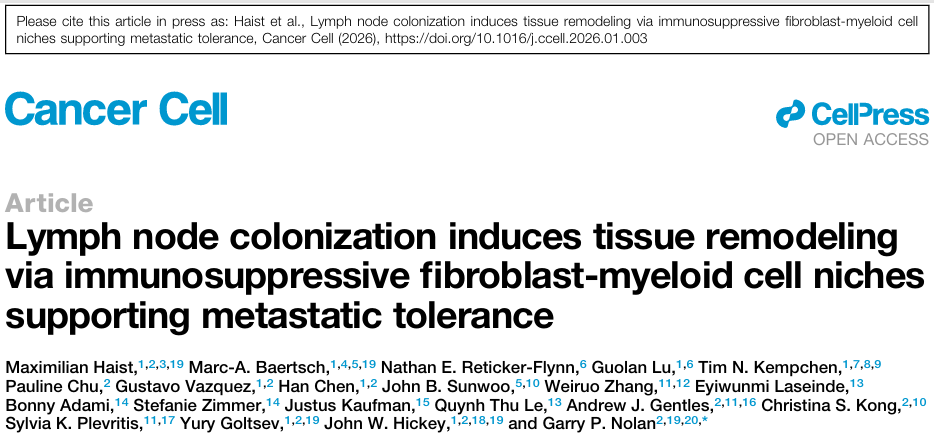

01 (CANCER CELL) 淋巴结定植通过免疫抑制性成纤维细胞-髓系细胞生态位诱导转移耐受的组织重塑

1. (CANCER CELL,IF:48.8) 淋巴结定植通过免疫抑制性成纤维细胞-髓系细胞生态位诱导转移耐受的组织重塑

01 (CANCER CELL) 淋巴结定植通过免疫抑制性成纤维细胞-髓系细胞生态位诱导转移耐受的组织重塑

1. (CANCER CELL,IF:48.8) 淋巴结定植通过免疫抑制性成纤维细胞-髓系细胞生态位诱导转移耐受的组织重塑